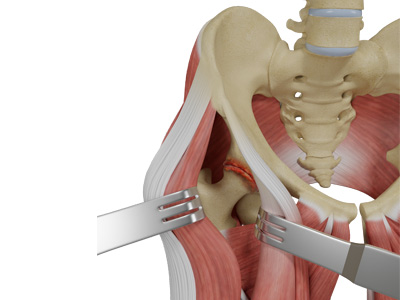

Muscles and Tendons

A long tendon called the iliotibial band runs along the femur from the hip to the knee and serves as an attachment site for several hip muscles including the following:

- Gluteals: These are the muscles that form the buttocks. There are three muscles (gluteus minimus, gluteus maximus, and gluteus medius) that attach to the back of the pelvis and insert into the greater trochanter of the femur.

- Adductors: These muscles are located in the thigh which helps in adduction, the action of pulling the leg back towards the midline.

- Iliopsoas: This muscle is located in front of the hip joint and provides flexion. It is a deep muscle that originates from the lower back and pelvis and extends up to the inside surface of the upper part of the femur.

- Rectus femoris: This is the largest band of muscles located in front of the thigh. They also are hip flexors.

- Hamstring muscles: These begin at the bottom of the pelvis and run down the back of the thigh. Because they cross the back of the hip joint, they help in extension of the hip by pulling it backward.

Muscle Sparing Anterior Hip Replacement Anterior Hip Replacement with Navigation

Minimally Invasive Total Hip Replacement Complex Primary Hip Replacement